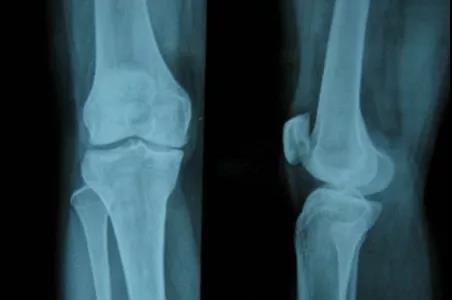

风湿性关节炎的检查?郑州风湿专科医院哪家好?

郑州风湿专科医院哪家好?风湿性关节炎怎样检查?对于很多疾病在 进行相应的检查后可以进一…[详情]